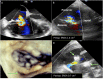

Tricuspid regurgitation in patients with left ventricular assist device (LVAD) has a significant impact on prognosis and quality of life, and its effects on liver and renal function could negatively impact planned heart transplantation. The aim of the present case is to report the feasibility and the clinical impact of tricuspid transcatheter edge-to-edge repair in LVAD patients as adjunctive bridge to transplantation strategy. A 59-year-old female patient previously treated with LVAD implantation (HeartMate III) and tricuspid valve repair with 32 mm rigid ring (Medtronic Contour 3D) as bridge to transplantation developed recurrence of significant tricuspid regurgitation with right ventricular decompensation needing inotropic support. Preoperative echo showed torrential tricuspid valve regurgitation Effective regurgitant orifice area(EROA 1.4 cm2 ) with suspicious of partial detachment of the prosthetic ring. The patient was successfully treated with transcatheter edge-to-edge repair with the MitraClip XTR device. Tricuspid regurgitation was reduced by 50% (postoperative EROA 0.7 cm2 ). She remained stable under continuous inotropic support with no other episodes of right ventricular decompensation and was successfully transplanted 30 days after the clipping procedure. Transcatheter treatment of tricuspid regurgitation in a patient with LVAD was an effective strategy to gain time and bridge the patient to heart transplantation.